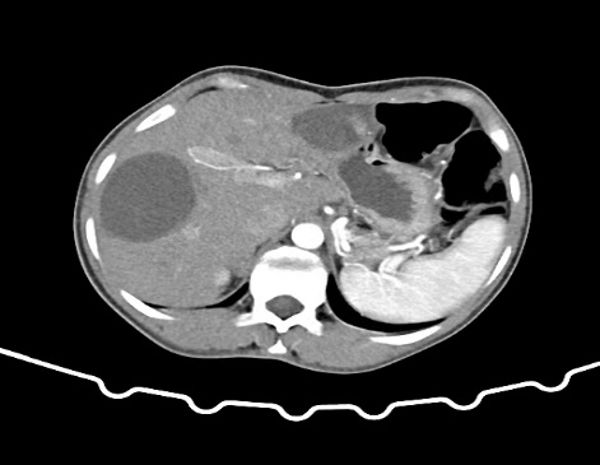

近期阿里地区人民医院收治一名28岁女性患者,体重40Kg,身高140cm,BMI20。以“体检发现肝包虫5年,肝区疼痛1年”之主诉入院。入院后完善B超及上腹部增强CT:肝脏S3段见大小8×7cm囊性病灶,S6、7段见大小约9×8cm 囊性病灶,诊断肝囊型包虫病(CE₃型)。我院援藏队员张立、何鑫、李洪亮及蔡艳组织MDT讨论,制定手术计划,考虑到患者年轻,肝脏体积小,药物作用慢,为防止包虫复发,及术后胆漏合并感染问题,决定采用外囊完整切除的根治性治疗。